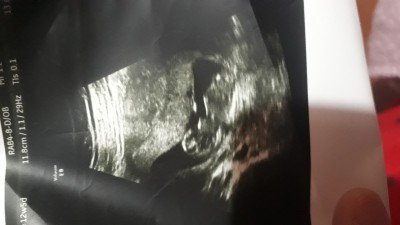

Ultrason görüntüsü ile cinsiyet tahmini yapabilir misiniz ?

Doktor kıza benziyor dedi ama bilmiyorum

16+4